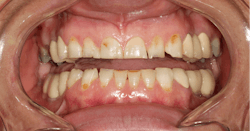

A 35-year-old female patient presented with esthetic concerns after a diagnosis of Sjögren's syndrome. Patient complaints included short appearance of teeth, stained teeth, and worn incisal edges (figures 1–2). Loss of vertical dimension of occlusion was noted as evidenced by shortened coronal structure and bilateral angular cheilitis (figure 3).

After the first phase consisting of caries control and periodontal treatment, the patient received soft- and hard-tissue crown lengthening by laser (figure 5). After an eight-week healing period, full-mouth cosmetic restorations were placed, which included full- and three-quarter-coverage e.max crowns and zirconia bridges (figures 6–7).